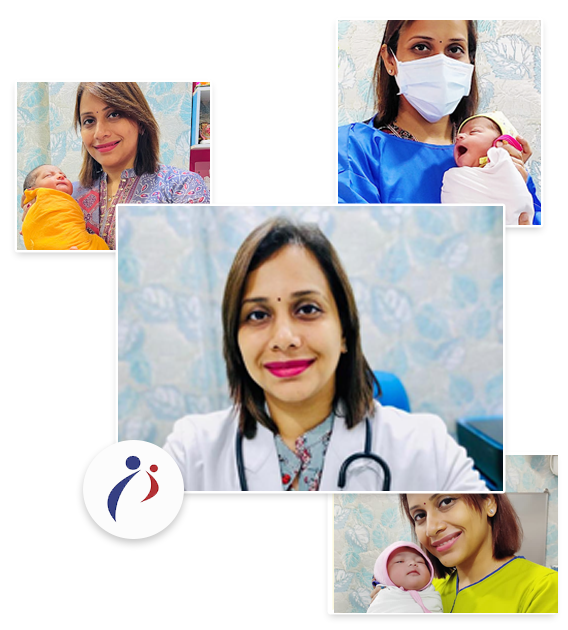

DR. HEMASHREE V. PATEL (MBBS, DNB, FMAS)

DNB, FMAS, DRM (GERMANY), DIP. COSMETIC GYN

Dr Hemashree V. Patel is a very well known Consultant Obstetrician & Gynaecologist practicing in Western Suburbs of Mumbai. She specializes in Laparoscopic & Hysteroscopic Surgeries and is Infertility & IVF Specialist. Throughout her service duration, she has helped many couples to become proud parents of healthy babies. She is trusted and approachable, which helps her patients to openly discuss their problems, and which makes the doctor’s job easy to provide a particular treatment, which is shared with her patients keeping it transparent and open. Her patient’s vouch for her services, humble nature, and dedication, Patients feedback and testimonials are assertions of her professionalism and work ethics.

Dr Hemashree V. Patel passed her FMAS examination conducted by AMASI in April 2018, she has done her DNB (Obs/Gyn) in April 2014 from Lawande’s Hospital and Research Centre, Goa. She did her MBBS from Rural Medical College, Loni under Maharashtra University Of Health Sciences, Nashik in June 2006.